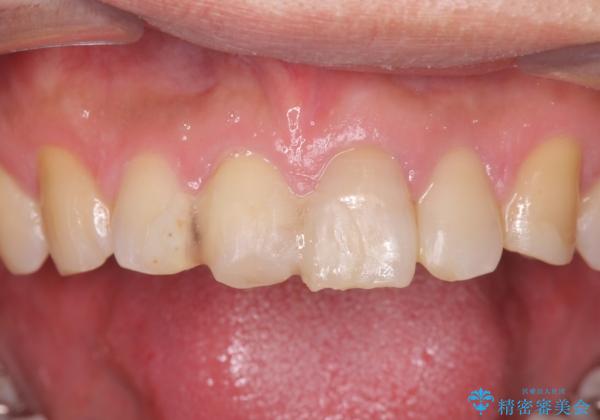

転んで前歯が欠けてぐらぐらに 歯の神経も死んでしまった

- 転倒して前歯を強打してかけてしまった、ぐらつくとのことで来院。

応急でみてもらった歯科医院で隣の歯と接着剤で留めてもらったとのこと。

歯の神経の状態を見たところ、前歯3本とも神経が死んでしまっていました。

また、左上犬歯の詰め物は途中で脱離し、セラミックでの修復をご希望されたため、一緒に治療しました。